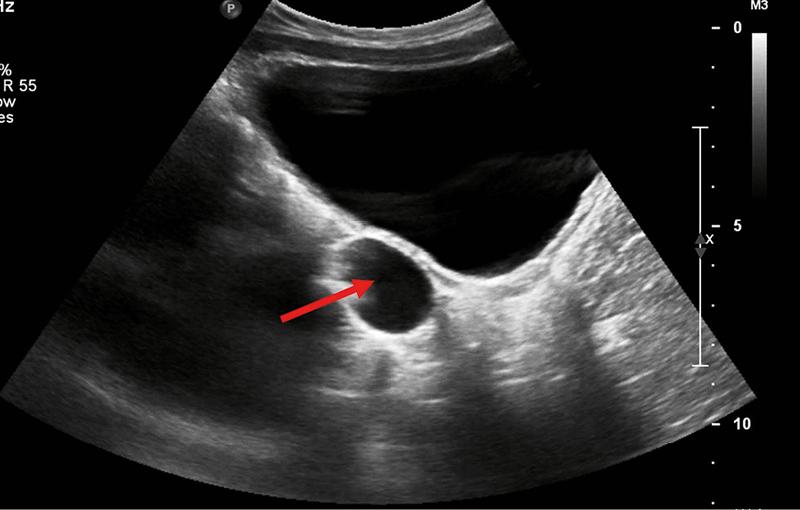

W kontekście diagnozowania torbieli podstawowym badaniem pozostaje ultrasonografia. To właśnie dzięki temu badaniu można ocenić zarówno wielkość, jak i charakter torbieli. Na USG lekarze sprawdzają, czy torbiel ma regularny kształt i cienkie ścianki, co zazwyczaj sugeruje, że mamy do czynienia z łagodną zmianą. W przeciwieństwie do tego, torbiele o nietypowym rozwoju mogą wskazywać na złośliwość, co wymaga dalszej obserwacji lub dodatkowych badań. Jeżeli lekarz zidentyfikuje torbiel, szczególnie u kobiet po 35. roku życia, zleci także dodatkowe badania krwi, takie jak test ROMA lub oznaczenie markera CA-125, aby wykluczyć ryzyko nowotworu.

Ultrasonografia jako kluczowe badanie w diagnostyce torbieli jajnika